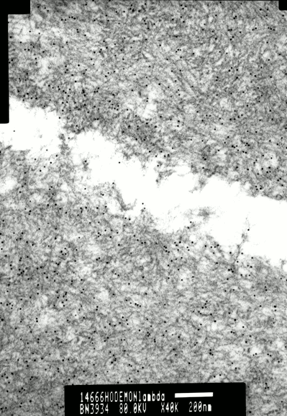

Exemples d’immunomarquage en MET

Les clichés suivants présentent deux coupes de glomérules, révélés par un antiserum et marqué avec billes d’or. Le premier cliché, à gauche est le témoin. Aucun marquage n’est observé, il n’y a donc pas d’amylose AL. Le second cliché, à droite est positif, révélant des dépots d’amylose répartis sur l’ensemble de la coupe.

Cette différence est encore plus marquée sur les clichés suivants :